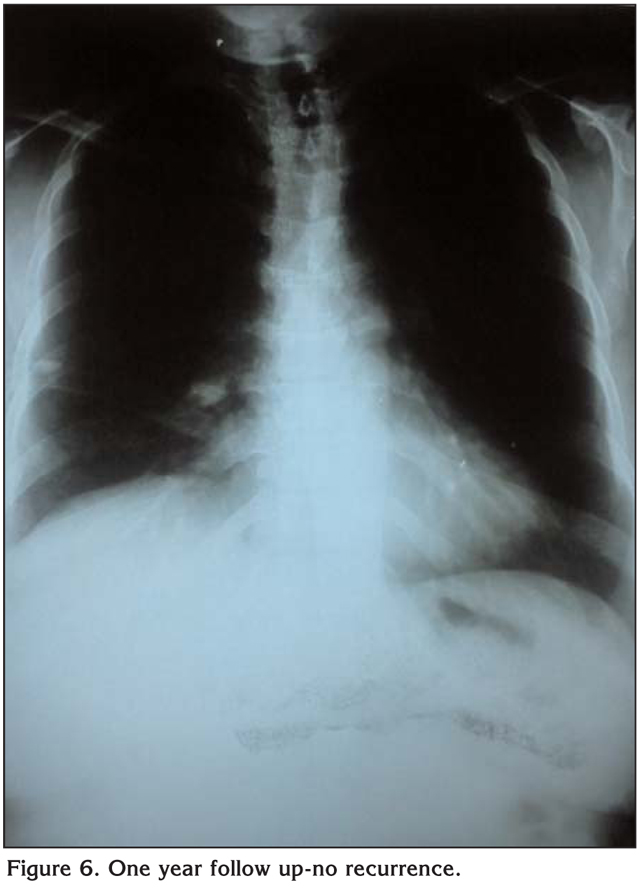

Hemostasis, closure of the post sites and using the anterior utility port as a site for chest tube drainage (Figure 4). Postoperative course was smooth with removal of the tube on the 2nd postoperative day and patient discharge home on the 5th day (Figure 5). Routine follow up visits showed nicely healed wound and no recurrence detected on 1 year follow up (Figure 6).

Figure 6